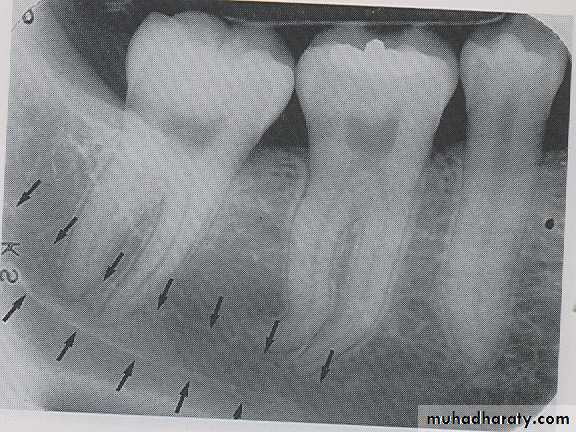

MANDIBULAR CANAL:

The mandibular canal is a tube like passage way through the bone that travels the length of the mandible, its extends from the mandibular foramen to the mental foramen and houses the inferior alveolar nerve and blood vessels. On radiograph the mandibular canal appears as a radiolucent band outlined by two thin radiopaque lines that represent the cortical wall of the canal.